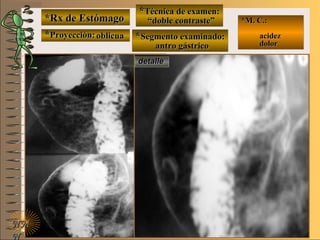

*Rx de Estómago*Rx de Estómago

**Proyección:Proyección:

**Técnica de examen:Técnica de examen:

**Segmento examinado:Segmento examinado:

*M. C.:*M. C.:

epigastralgiaepigastralgia

melenamelena

NMNM

detalledetalle

frentefrente

““doble contraste”doble contraste”

antro gástricoantro gástrico

A-A-El examen es normal o patológico?El examen es normal o patológico?

Examen patológico de estómago con técnica deExamen patológico de estómago con técnica de

doble contraste en proyección de frentedoble contraste en proyección de frente

B-B-La patología es congénita o adquirida?La patología es congénita o adquirida?

Patología adquiridaPatología adquirida

C-C- Dicha patología es orgánica, funcional o mixta?Dicha patología es orgánica, funcional o mixta?

Patología adquirida orgánicaPatología adquirida orgánica

D-D-La misma es neoplásica o no neoplásica?La misma es neoplásica o no neoplásica?

Patología adquirida orgánica no neoplásicaPatología adquirida orgánica no neoplásica

E-E-Puede describir la o las imágenes patológicas?Puede describir la o las imágenes patológicas?

Se identifican en antro gástrico múltiplesSe identifican en antro gástrico múltiples imáge-imáge-

nes mixtasnes mixtas UNTUNT : elevado (inflamación) y: elevado (inflamación) y

deprimidas (erosión) focales compatibles condeprimidas (erosión) focales compatibles con

una gastritis madura completauna gastritis madura completa